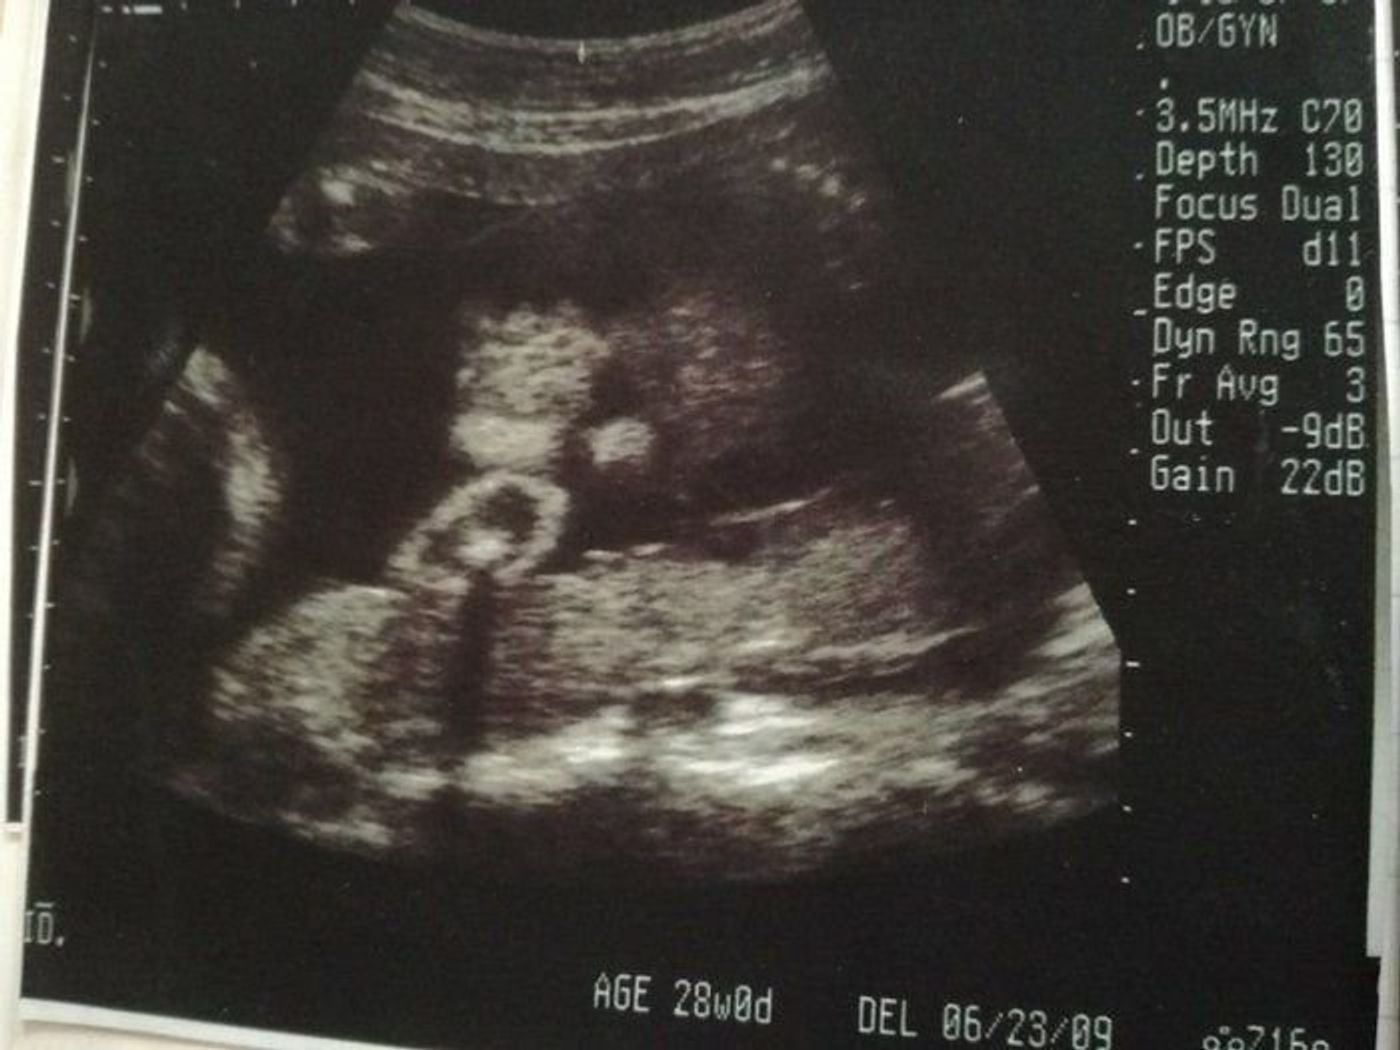

前回の記事『妊娠28週逆子と後期つわり』こんにちは、remocoです。 4/19〜妊娠28週目に突入しました 妊娠8ヶ月、つい ameblojp remocoの暮らし妊娠週28w2d 左側からの横顔です♬︎♡ 目鼻立ちがくっきりしていてとても可愛いです(,,> ,,)♡ BPD70 FL49 AC23 推定体重1150g程で標準との事でした〜 *˚ 前回26wの健診の時に逆子が治ってましたが、今回またまた逆子ちゃんになってました( ˊᵕˋ ;) 長男、次男 妊娠8ヶ月で逆子だった時 妊娠後期に入ってからの逆子だと、分娩に影響があるのでは?と心配になってくるかもしれません。 妊娠8ヶ月、妊娠28週目ぐらいであれば後期に入ったところです。 まだ子宮内に余裕があり動き回りやすい時期です。

妊娠28週 3 6日 のエコー写真 体験談